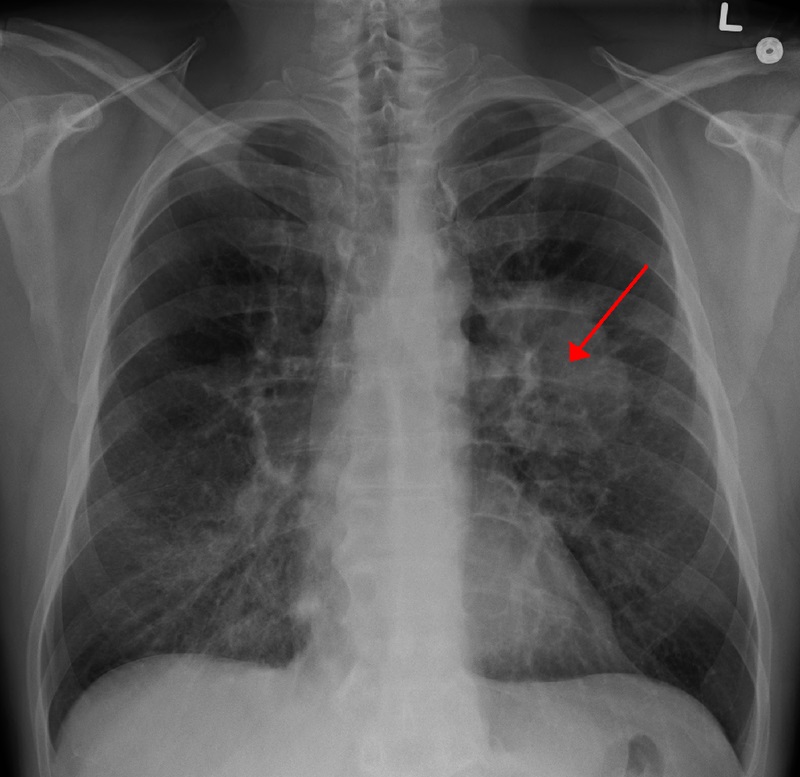

Различают несколько периодов развития болезни. На ранних стадиях заболевание не проявляется никакими симптомами, опухоль имеет размер до  3 см, обнаруживается только на рентгенологическом обследовании. Также возможно наличие общих симптомов: слабость, утомляемость, потеря веса,  субфебрильная температура. Появление специфических симптомов может свидетельствовать о более поздней стадии заболевания, при которой происходит повреждение сосудов и прорастание опухоли на плевру. Специфическими симптомами заболевания являются: сильный продолжительный кашель (может быть с выделением мокроты или сухой), кровохаркание, одышка, боль в грудной клетке, синюшность лица и его отек.

Основная проблема ранней диагностики рака легкого заключается в длительном периоде скрытого течения заболевания. Специфические симптомы появляются уже на более поздних и тяжелых стадиях.  Диагностика при подозрении на рак легкого включает в себя физикальное обследование, рентгенологическое исследование, бронхографию, КТ легких, биохимический анализ крови, цитологическое исследование мокроты, эндоскопическое бронхологическое обследование.